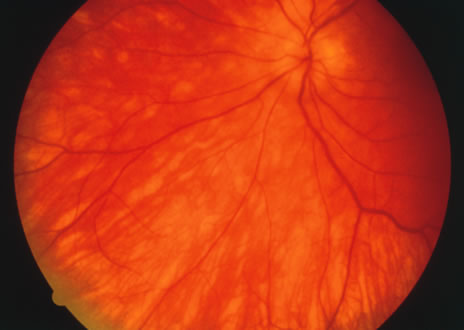

Fig. 11. A. Subretinal fibrosis in a case of multifocal choroiditis. B. Fellow eye showing classic coalescent hyperpigmented chorioretinal scars of multifocal choroiditis. These scars also can be seen in presumed histoplasmosis syndrome, but the subretinal fibrosis is extremely rare in presumed ocular histoplasmosis syndrome (POHS).